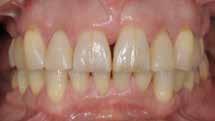

Den kliniske undersøgelse viser harmoniske ekstraorale sagittale forhold med skeletalt dybt bid (Fig. 1A, D). Hendes smil er alderssvarende med en eksponering på 8/10 af overkæbeincisiverne, mens smilets bredde er smalt med synlige mørke laterale rum (Fig. 1D). Underkæbeincisiverne er synlige under tale. Der ses neutrale okklusale forhold ved hjørnetænderne og neutrale pladsforhold i overkæben, men udtalt trangstilling i underkæben især lokaliseret i regio 1-1 (Fig. 1C).

Sliddet klassificeres som grad 2 (moderat tandslid) på de centrale incisiver i overkæbe og underkæbe. Det kan anses som patologisk, da det er atypisk for patientens alder, giver anledning til smerte/ubehag, og giver patienten et æstetisk problem. Der ses infraktioner af overkæbeincisiverne. Der ses endvidere en udtalt Spee-kurve i underkæben og ingen interincisal afstøtning på 2-2 med let ganepåbidning.

I samråd med patienten og egen tandlæge* afstemmes forventningerne, inden der bestilles refinement alignere. Nivelleringen af alle tænder i tandbuerne, smilelinje og -kurve samt den bukko-lingvale position af incisiverne foretages og efterfølges af retainers lingvalt på over- og underkæbeincisiver (Fig. 3 A-D). Hele behandlingen udføres under løbende kommunikation med patient og egen tandlæge*, der udfører den efterfølgende rekonstruktion med direkte plast (Fig. 4 A-D). Behandlingsvarigheden har været to år og to måneder, hvor ortodontien har forløbet over 21 måneder. Der har været anvendt et første sæt på 66 alignere samt yderligere to sæt med ni refinement alignere. Tandblegning og direkte plastrekonstruktion er udført af egen tandlæge* (Fig. 5 A-F).

Fig. 5. A, B. Smil og kæbeforhold før og efter. Et bredere smil med korrektion af de laterale mørke rum. C-F. Harmonisk hældning af overkæbe- og underkæbeincisiver, rekonstruktion af den tabte tandsubstans efter nivellering af gingivaniveau og optimal bukko-lingval placering til direkte plastbehandling.

5. A, B. Smile and jaw relationships before and after. A wider smile with correction of the lateral dark spaces. C-F. Harmonious inclination of the upper and lower jaw incisors, reconstruction of the lost tooth substance after leveling the gingival level, and optimal bucco-lingual positioning for direct plastic treatment.